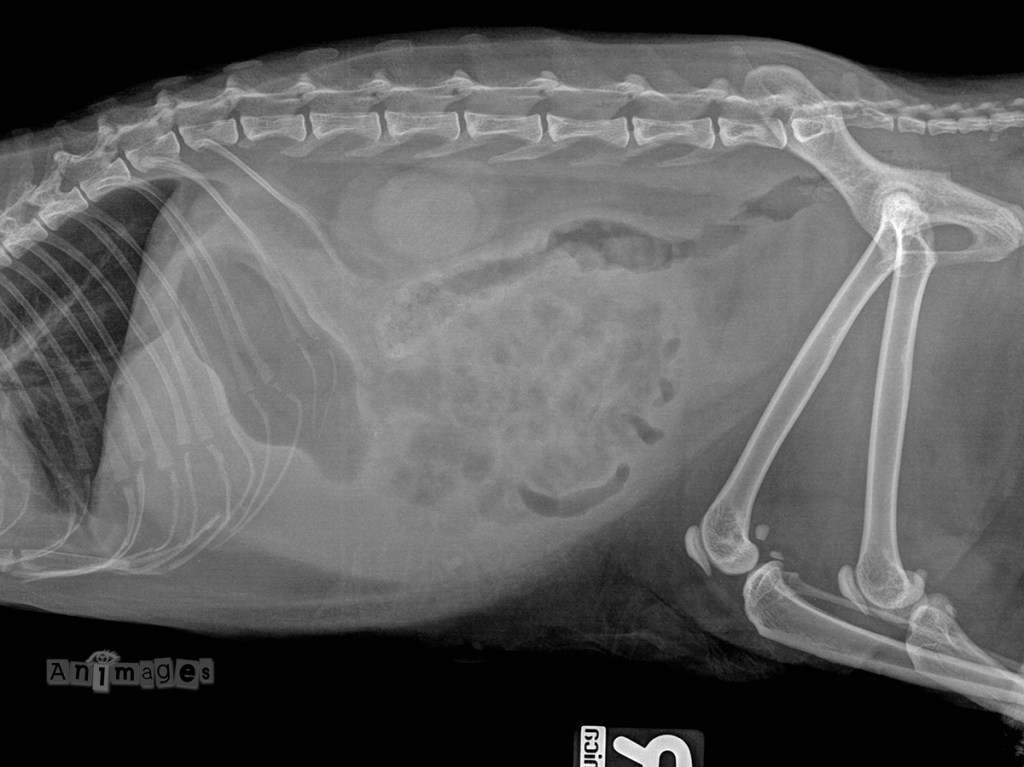

latérale droite